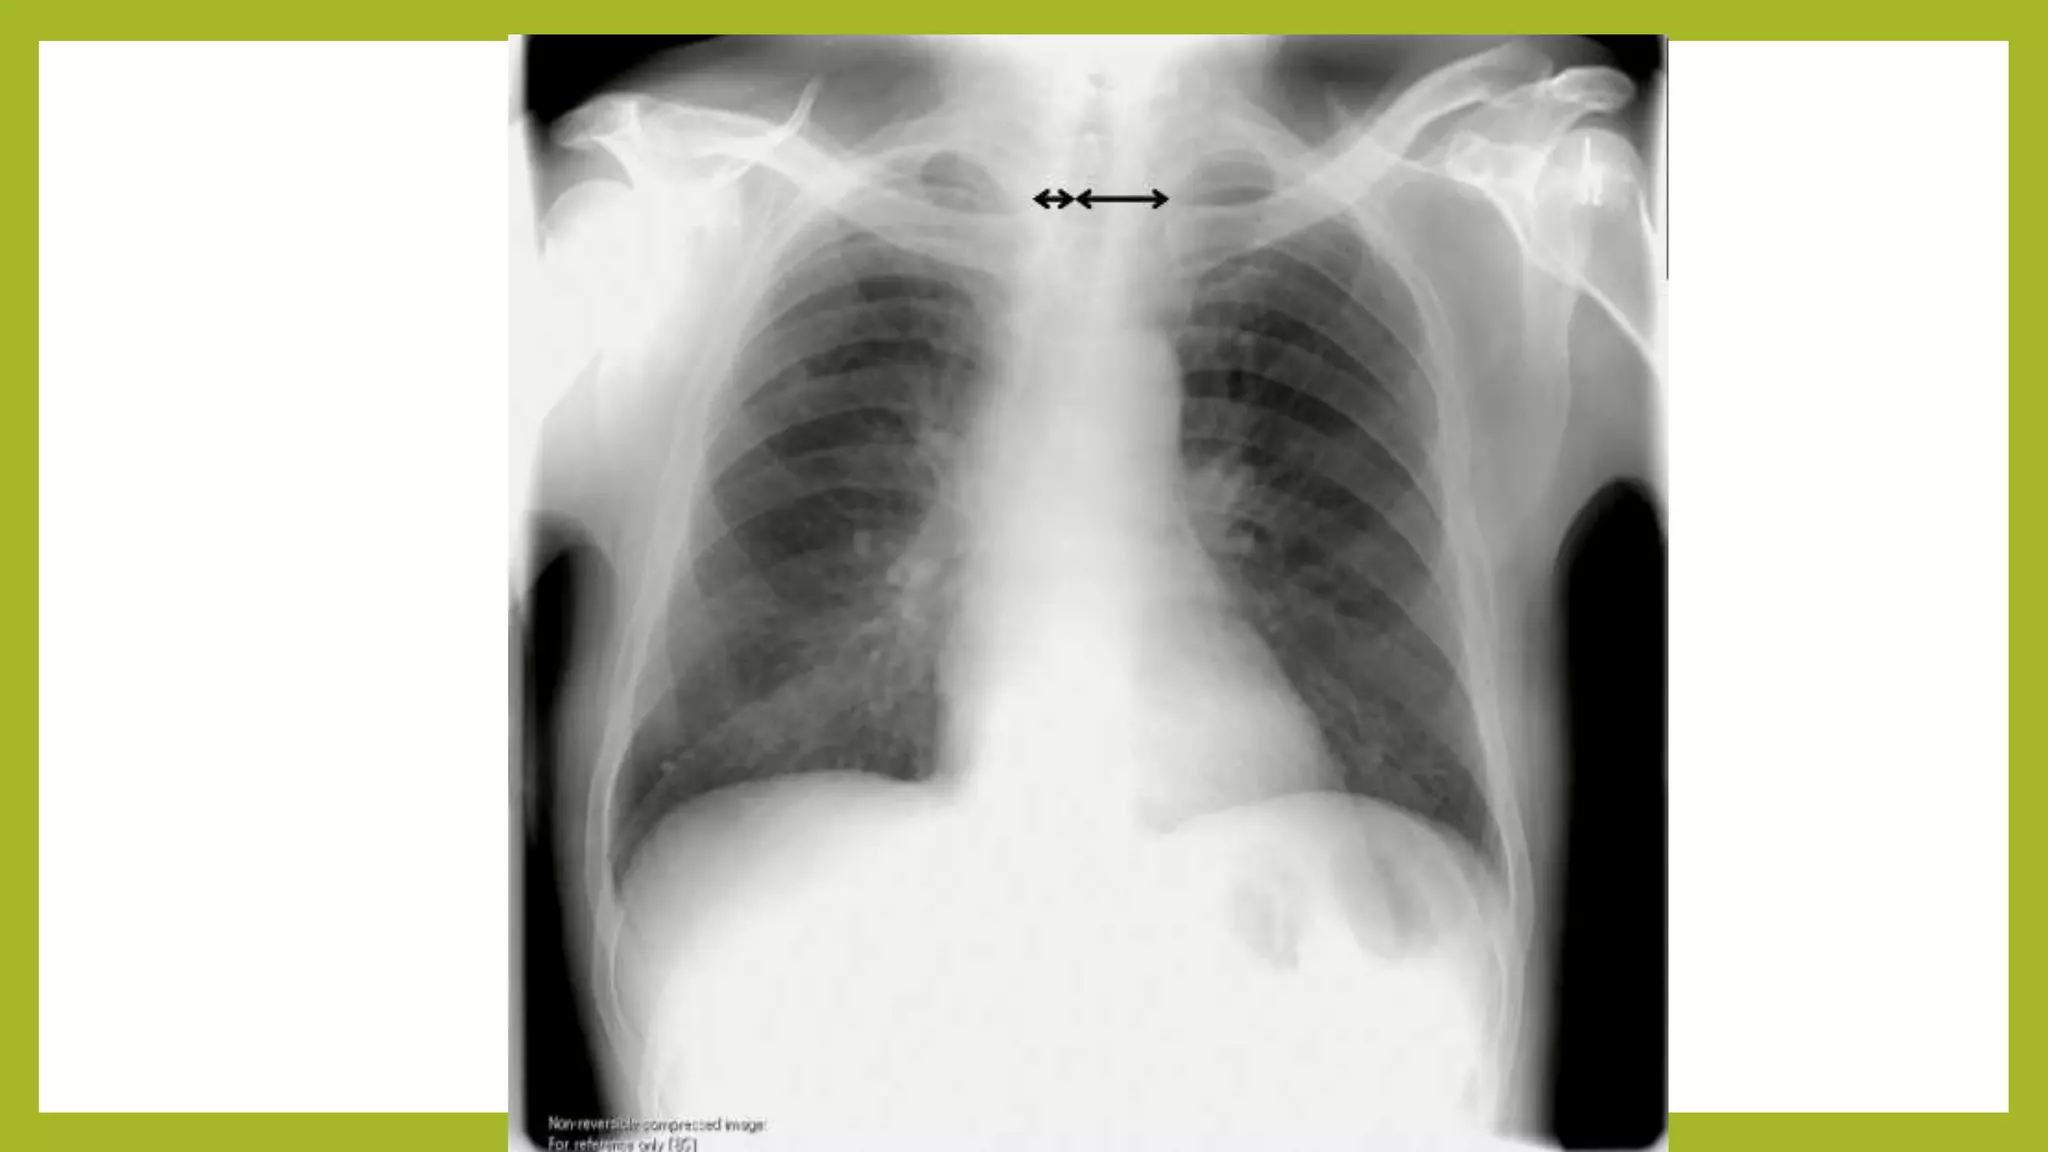

The document provides guidance on approaching and interpreting chest x-rays (CXR). It outlines steps to check the name, date and quality of the film, systematically scan the CXR looking for abnormalities, and determine if the lungs appear too white or black. Specific signs are described to help localize abnormalities, including the cardiac silhouette sign and pleural effusion signs. Examples are given of respiratory distress syndrome, tetralogy of fallot, transposition of great arteries, and total anomalous pulmonary venous return. The take home message is to summarize positive findings, compare to prior CXRs if available, and confirm findings with a radiologist.